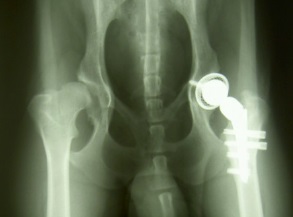

Protesi, quando è necessario operarsi?

protesi all'anca

Le possibili alterazioni a carico delle articolazioni Le diverse patologie d’interesse ortopedico, nella maggior parte dei casi, possono essere trattate con mezzi fisici non cruenti, volti al miglioramento del quadro clinico del paziente. L’uso di trattamenti non chirurgici può ritenersi valido in tutti i casi in cui è possibile disinfiammare muscoli e articolazioni, tramite l’applicazione … Leggi tutto